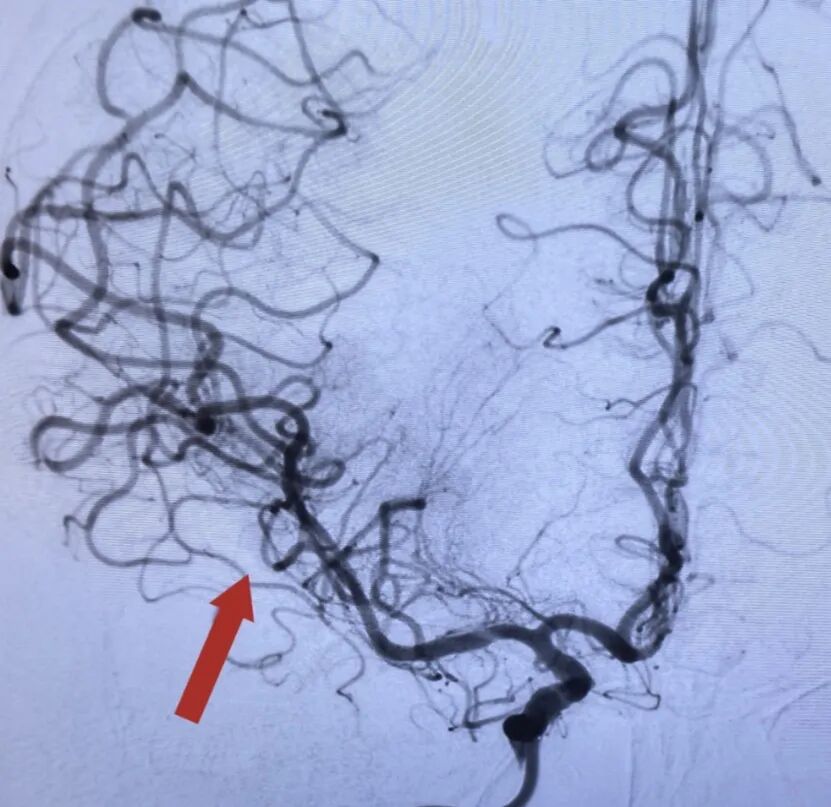

入院时,患者已出现意识障碍、双眼凝视、一侧肢体瘫痪等严重脑卒中的危重表现。头颅CT+CTP影像显示“右侧大脑中动脉M1段急性闭塞”,这是前循环卒中最凶险的类型之一,死亡率及致残率极高,病情进展迅猛,若不及时开通血管,每一分钟的延误都意味着数百万脑细胞的死亡和不可逆功能丧失的可能。

闭塞的大脑中动脉

时间就是大脑,时间就是生命!面对危急情况,急诊医学科团队宋欣峰、孙潇东、胥滨芳与放射科王良杰迅速集结、当机立断,在与家属充分沟通并取得同意后,开启绿色通道,立即为患者施行急诊血管内取栓治疗。在先进的数字减影血管造影(DSA)引导下,医生们凭借高超的技术,将一根细如发丝的导管精准抵达颅内闭塞血管,成功取出堵塞血管的血栓,实现了血流的瞬间再通。

完全开通的大脑中动脉